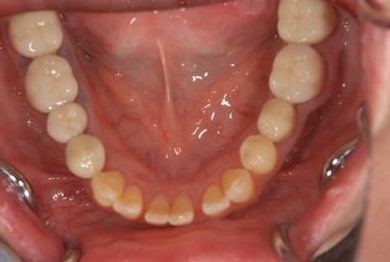

| 性別/年齢 | 女性 / 51歳 | ||||||||||||||||||||||||||||||||

| 主訴 | 前の歯の治療後の変色が気になる。詰め物がとれた箇所あり。痛みあり。 | ||||||||||||||||||||||||||||||||

| 治療方針 | セラミック治療にて、審美的回復を行う。 | ||||||||||||||||||||||||||||||||

| 治療内容 | オールセラミッククラウン7本(オールセラミック用土台1本)、ハイブリッドセラミッククラウン10本(ハイブリッドセラミック用土台9本)、ハイブリッドセラミックインレー1本 | ||||||||||||||||||||||||||||||||

| 総治療費 | 961,800円 | ||||||||||||||||||||||||||||||||

| 治療期間 | 10ヶ月 |